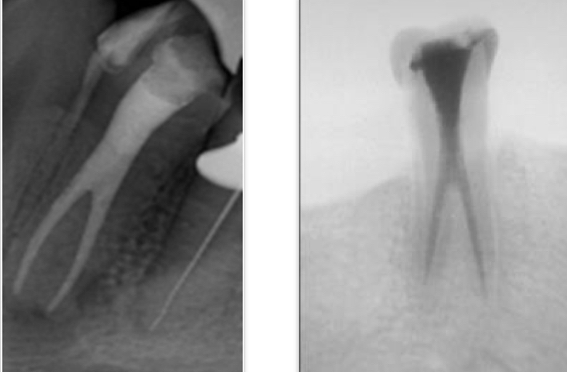

What are dilacerations?

Sharp curve in root suggest trauma or bony interference during root formation

What is the first cause of RCT failure in lateral incisors?

Apical curvature in DP direction- files tend to straighten so don’t instrument apical third